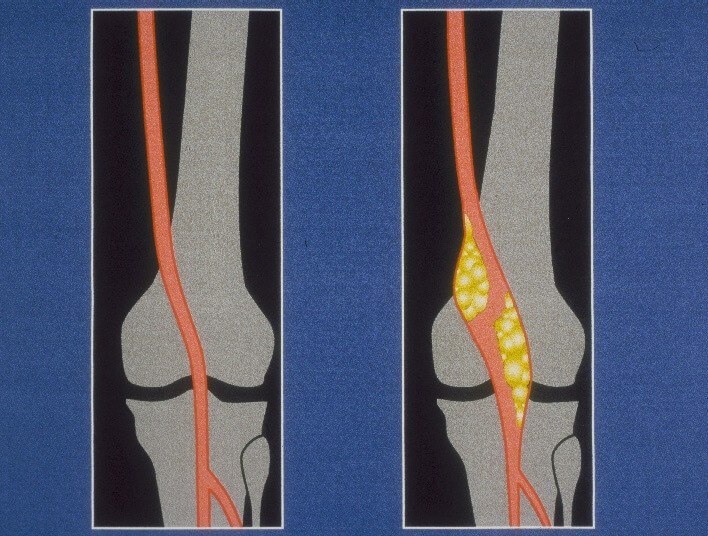

Comment: This is a nice example of a popliteal artery aneurysm on angiography. The dilatation of the lumen is subtle on the LLE angiogram, but the actual appearance of the aneurysm is seen above diagrammatically. In addition, the tendency for bilateral popliteal artery aneurysms is seen in this patient as is the risk of distal embolization.